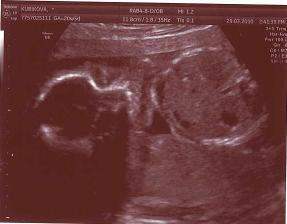

29.3.2010 Velký utz ve 20tt